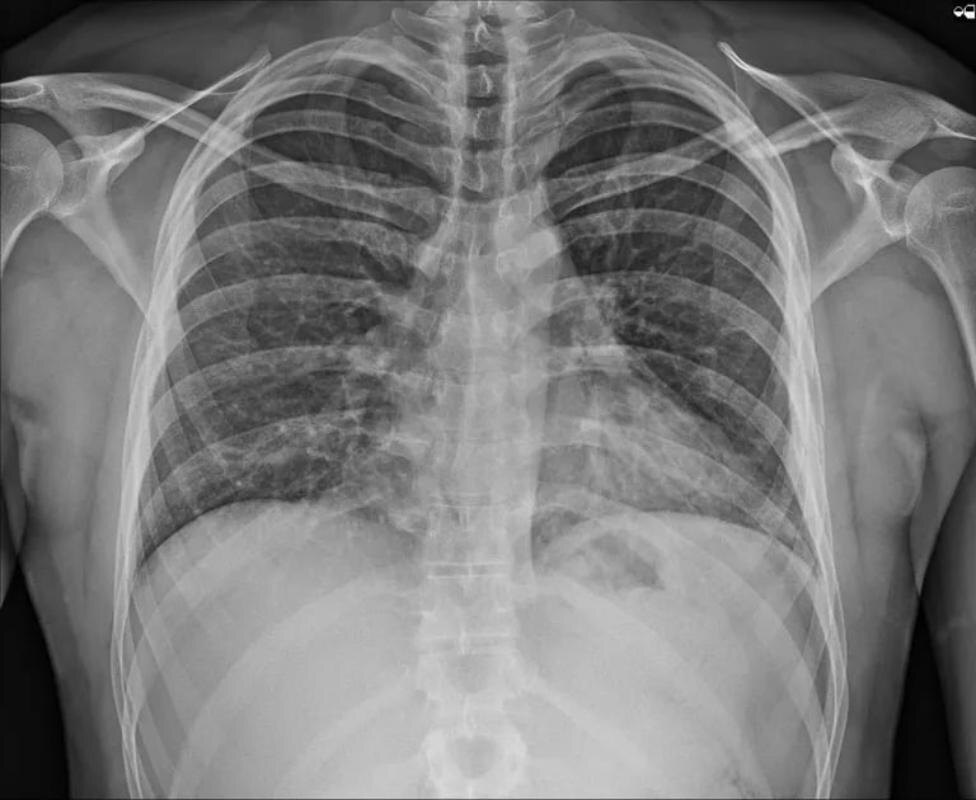

По данным пресс-службы медучреждения, ежегодно в травмбольницу попадает до двухсот пациентов с переломами ребер. Хирургические вмешательства в условиях непосредственной близости к легким довольно рискованны и имеют множество ограничений. Поэтому врачи выбирают консервативное лечение, при котором на восстановление пациента уходит очень много времени.

- Новая техника операции более безопасна. Ее название – малоинвазивная ретроградная интрамедуллярная временная фиксация переломов ребер, - сообщают в б

- Новая техника операции более безопасна. Ее название – малоинвазивная ретроградная интрамедуллярная временная фиксация переломов ребер, - сообщают в больнице.

Специально разработанный фиксатор заводят в кость особым способом, не травмируя окружающие мягкие ткани. Пациент избавляется от болевых симптомов, в том числе, во время дыхания. При этом сокращается процесс реабилитации.

-Принимая во внимание особенности анатомии грудной клетки, мы адаптировали к хирургическому лечению переломов ребер основы малоинвазивного остеосинтеза переломов костей опорно-двигательного аппарата. Используя этот метод, нам удалось значительно снизить количество осложнений у пациентов с травмой грудной клетки, сократить период искусственной вентиляции лёгких, уменьшить период нетрудоспособности пациентов, - объяснил Сергей Глиняный.

Фото: пресс-служба Сургутской травмбольницы